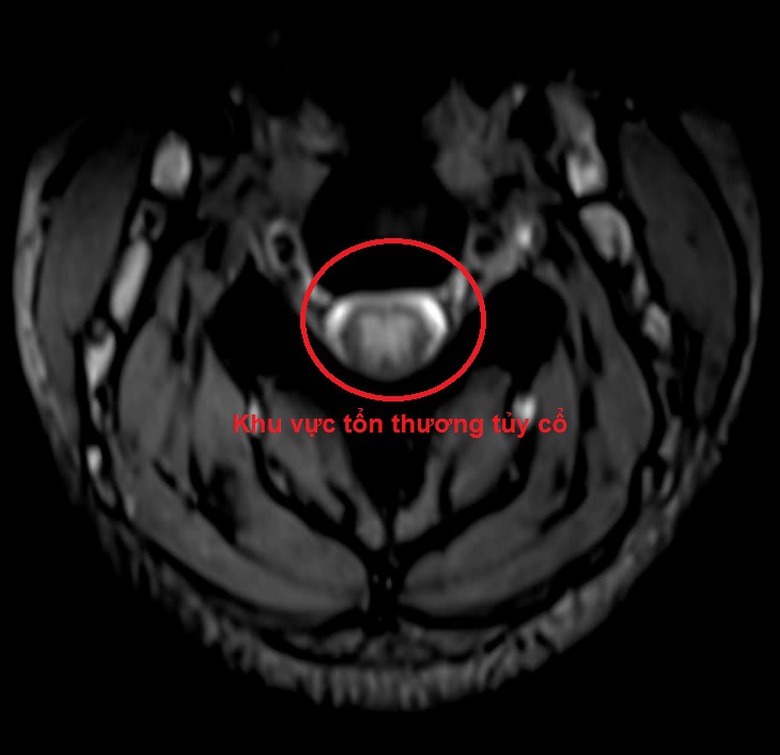

Hình ảnh tổn thương tủy cổ dẫn đến yếu liệt các chi sau khi hút 15 quả bóng cười của 1 nữ sinh ở Vĩnh Phúc. (Ảnh minh họa và BVCC).

Nữ sinh này nhập viện trong tình trạng tê bì, giảm cảm giác tứ chi; chân nặng hơn tay, liệt mềm chân cơ lực 2/5, gặp khó khăn trong vận động, không thể đi lại, phải di chuyển bằng xe lăn; yếu hai tay...

Sau xét nghiệm, chiếu chụp bệnh nhân được chẩn đoán, tổn thương thần kinh ngoại vi giai đoạn bán cấp do lạm dụng bóng cười và được chỉ định điều trị bằng thuốc tăng dẫn truyền thần kinh, vitamin B12 liều cao. Sau 10 ngày điều trị, người bệnh đã cải thiện hơn, đi lại, vận động được, đỡ tê bì…

Chính vì vậy, trên những người bệnh có triệu chứng tê bì, dị cảm tứ chi, việc khai thác tiền sử lạm dụng bóng cười, khám lâm sàng và cận lâm sàng đầy đủ, đặc biệt là MRI cột sống cổ và đo dẫn truyền thần kinh sẽ giúp cho việc chẩn đoán chính xác, từ đó sẽ phục hồi chức năng vận động của người bệnh một cách tối đa.